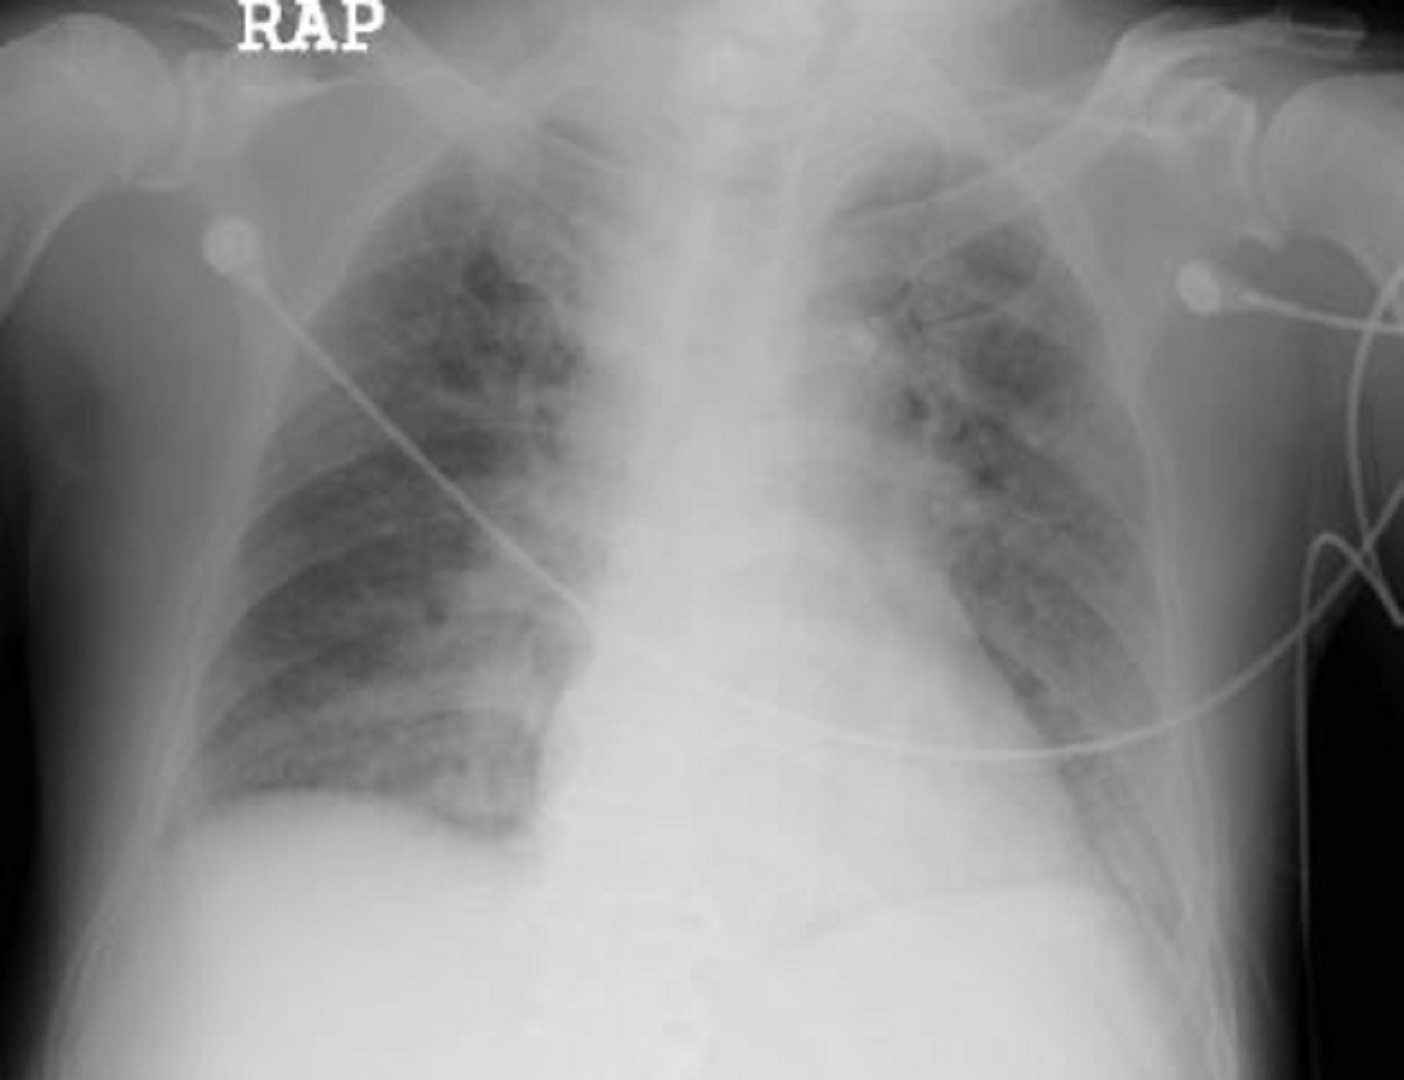

폐부종은 폐에 과도한 체액이 쌓이는 질환입니다. 호흡 곤란을 유발하여서 심각한 경우 생명을 위협할 수 있습니다. 주로 심장 질환과 관련이 깊지만, 감염, 신장 질환, 약물 부작용 등 다양한 원인에 의해 발생할 수 있습니다. 본 글에서는 폐부종의 주요 원인, 나타나는 증상, 그리고 효과적인 치료 방법에 대해서 자세히 알아보겠습니다.

폐부종이 발생하면 가장 먼저 호흡 곤란이 나타납니다. 초기에는 운동할 때 숨이 차는 정도로 시작되지만, 상태가 악화되면 가만히 있을 때도 숨이 차고, 심할 경우 숨을 들이마시기조차 어려운 상태에 이르게 됩니다. 이는 폐에 체액이 차면서 산소 교환이 원활하게 이루어지지 않기 때문입니다.

또한, 폐부종 환자들은 기침을 자주 하게 되면서 이때 거품이 섞인 분홍색 가래가 나올 수 있습니다. 이는 폐 속 체액이 기도로 유입되었음을 의미합니다. 그리고 응급 처치가 필요할 수 있습니다. 심한 경우에는 청색증(입술이나 손끝이 파랗게 변함)이 나타날 수 있습니다. 그리고 이는 산소 부족이 심각하다는 신호입니다.

폐부종이 심한 경우 의식 저하, 심한 불안감, 차가운 땀, 현기증 등이 동반될 수 있으며, 이러한 증상은 응급 치료가 필요하다는 신호이므로 즉시 병원을 방문해야 합니다.